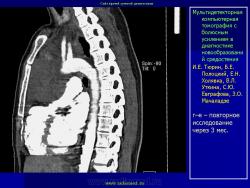

Средостение.  "Опухолевый рост".

Продолжение.